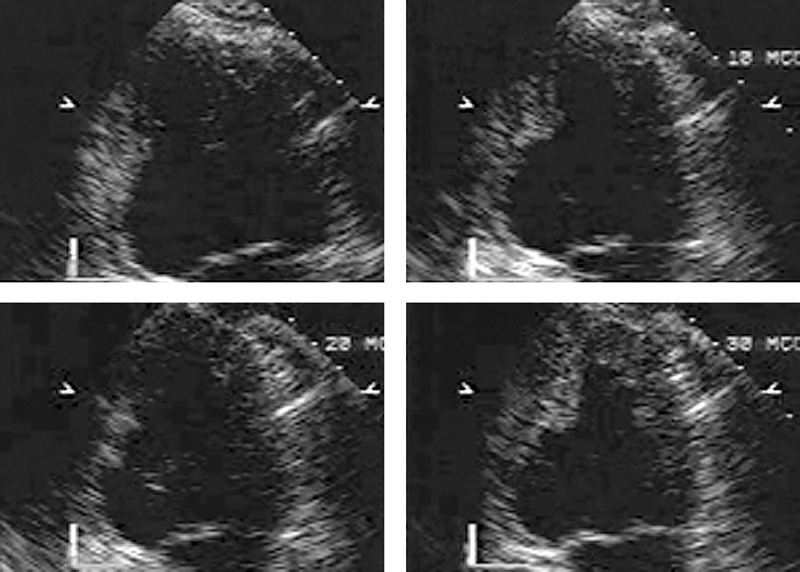

فحوصات تشخيصية لبعض امراض القلب والشرايين التاجية